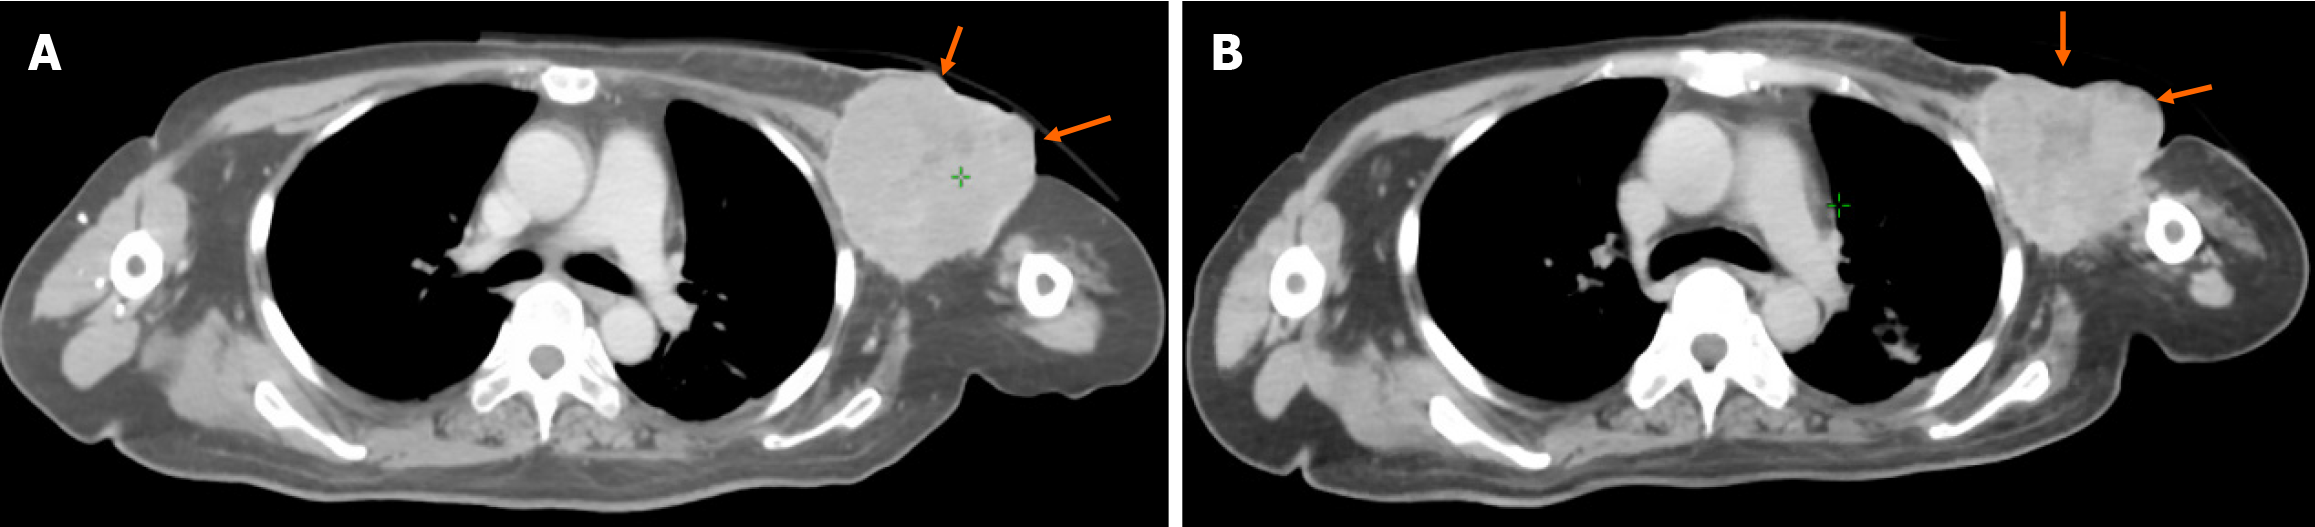

An enhanced CT scan performed on February 21, 2024, showed a large left ALN with a maximum cross-sectional dia